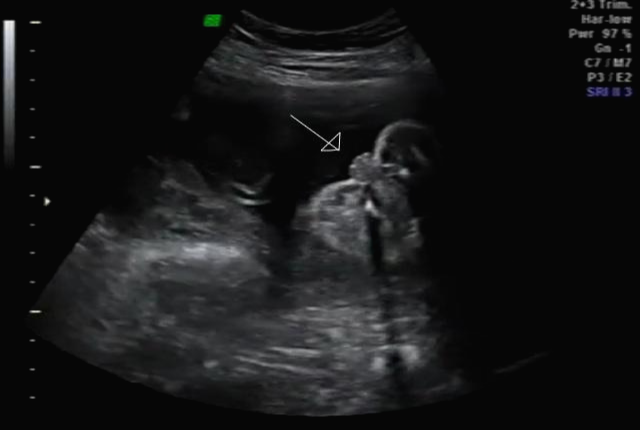

24주 차에 다시 사설로 초음파 검사를 받으러 갔는데 초음파를 보시더니 정밀 초음파 검사 때 성별 딸이 었냐 아들이 었냐 물어보시길래 딸이라고 말을 하니 미안하다고 지금 보니 딸이라고 하길래 이때는 정밀 초음파 검사 후 한 달 뒤여서 상관없다고 ㅋㅋㅋㅋㅋ 아들인지 딸인지 뭐가 중요하냐고 아이만 건강하면 된다고 하니 ㅎㅎ 그때서야 웃으시더라고요 ㅎㅎ 많이 미안했던 모양... 워낙 아이 건강상태를 꼼꼼하게 잘 봐주시고 만족할만하게 아이 얼굴 초음파 사진을 찍어주셔서 다 용서가 됐어요 ㅎㅎ